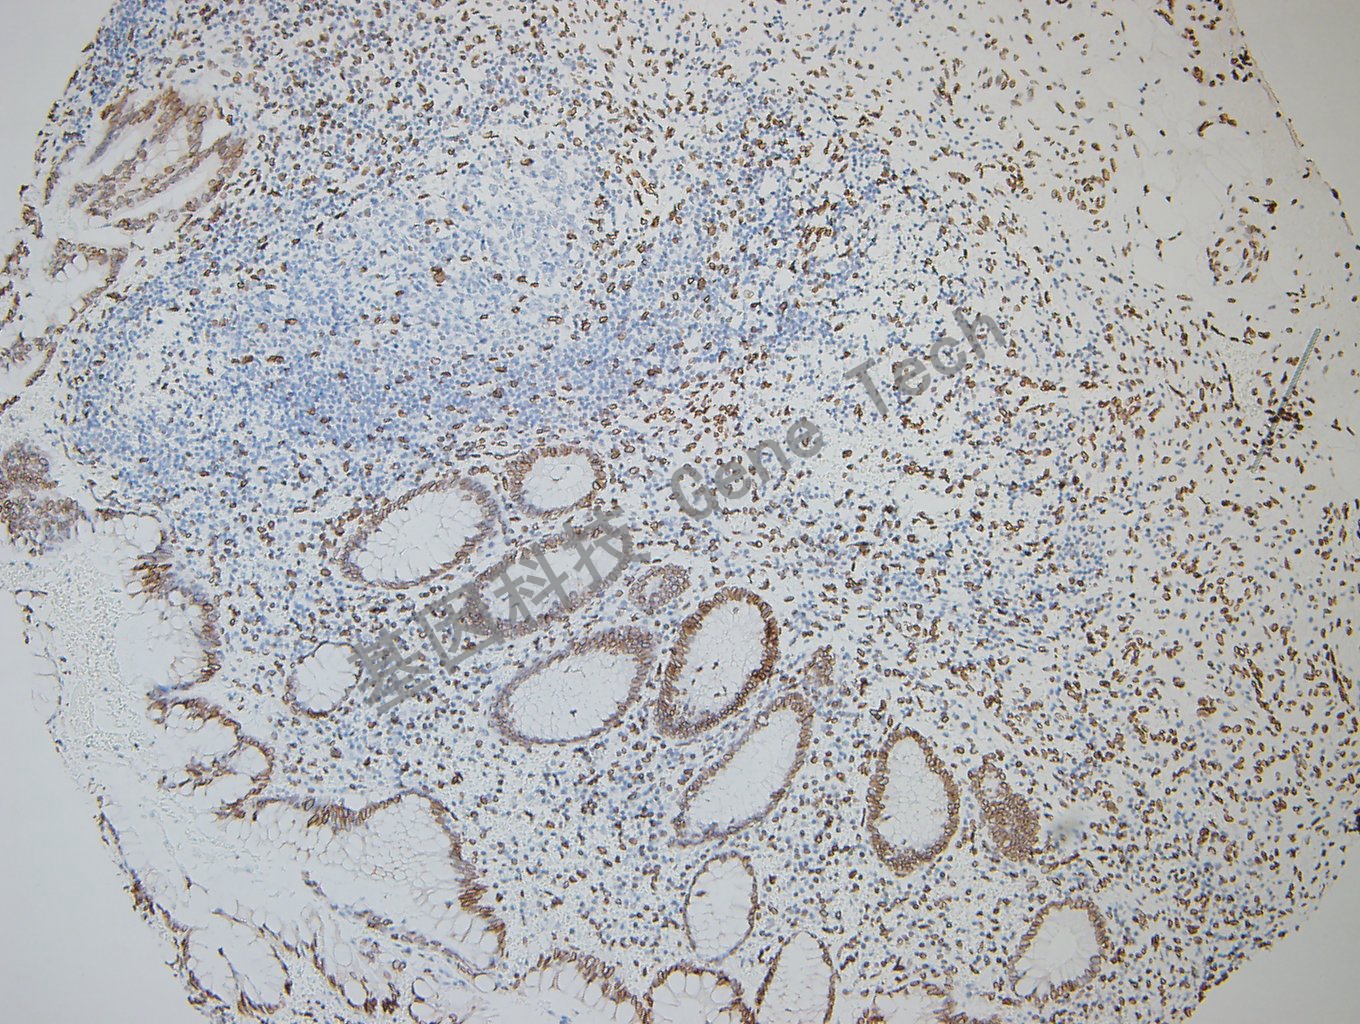

阑尾石蜡切片,用 GATA2(GT2320)染色,细胞核阳性,DAB 显色。